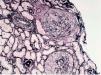

The anatomical pathology described a total of 49 glomeruli, three of them sclerosed and the structure of the others was extensively affected. Fibrinoid necrosis and extracapillary cell and circumferential proliferation were found in 100% of the glomeruli. The small vessels also had necrotising vasculitis. The direct IF study provided a linear and diffuse positive in the glomerular basement membrane, with IgG positive and the rest of the antibodies negative. In summary, extracapillary glomerulonephritis was detected with intense involvement of 100% of the glomeruli of the sample and IF typical of anti-GBM Ab-mediated extracapillary glomerulonephritis (type I), see Figures 1 and 2.

Figure 1. Silver technique